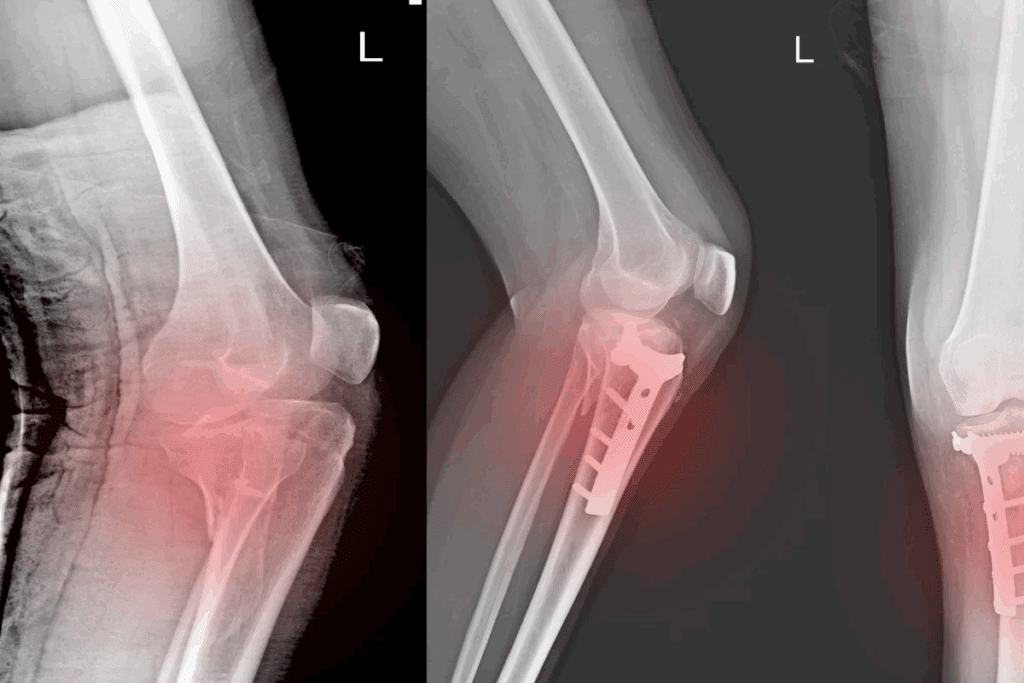

X-Ray Confirmation

X-rays are the top choice for finding bone fractures. They show the bone’s structure clearly, helping doctors spot fractures and other bone issues. X-rays are fast and easy to get, making them a vital first step.

Surgical Interventions

More complex fractures need surgery. This includes fractures that are displaced, comminuted, or involve joints. Surgical options include:

- Internal Fixation: Plates, screws, or rods are used to stabilize the bone internally.